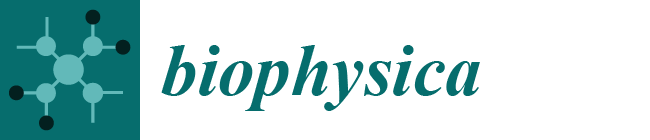

2.2. MR Methodology

- Spectroscopy NDB: in subcutaneous tissue and visceral tissue.

- Imaging NDB (pixel by pixel): regions of interest were drawn in subcutaneous tissue and visceral tissue; mean values were recorded.

- Imaging (global): NDB.